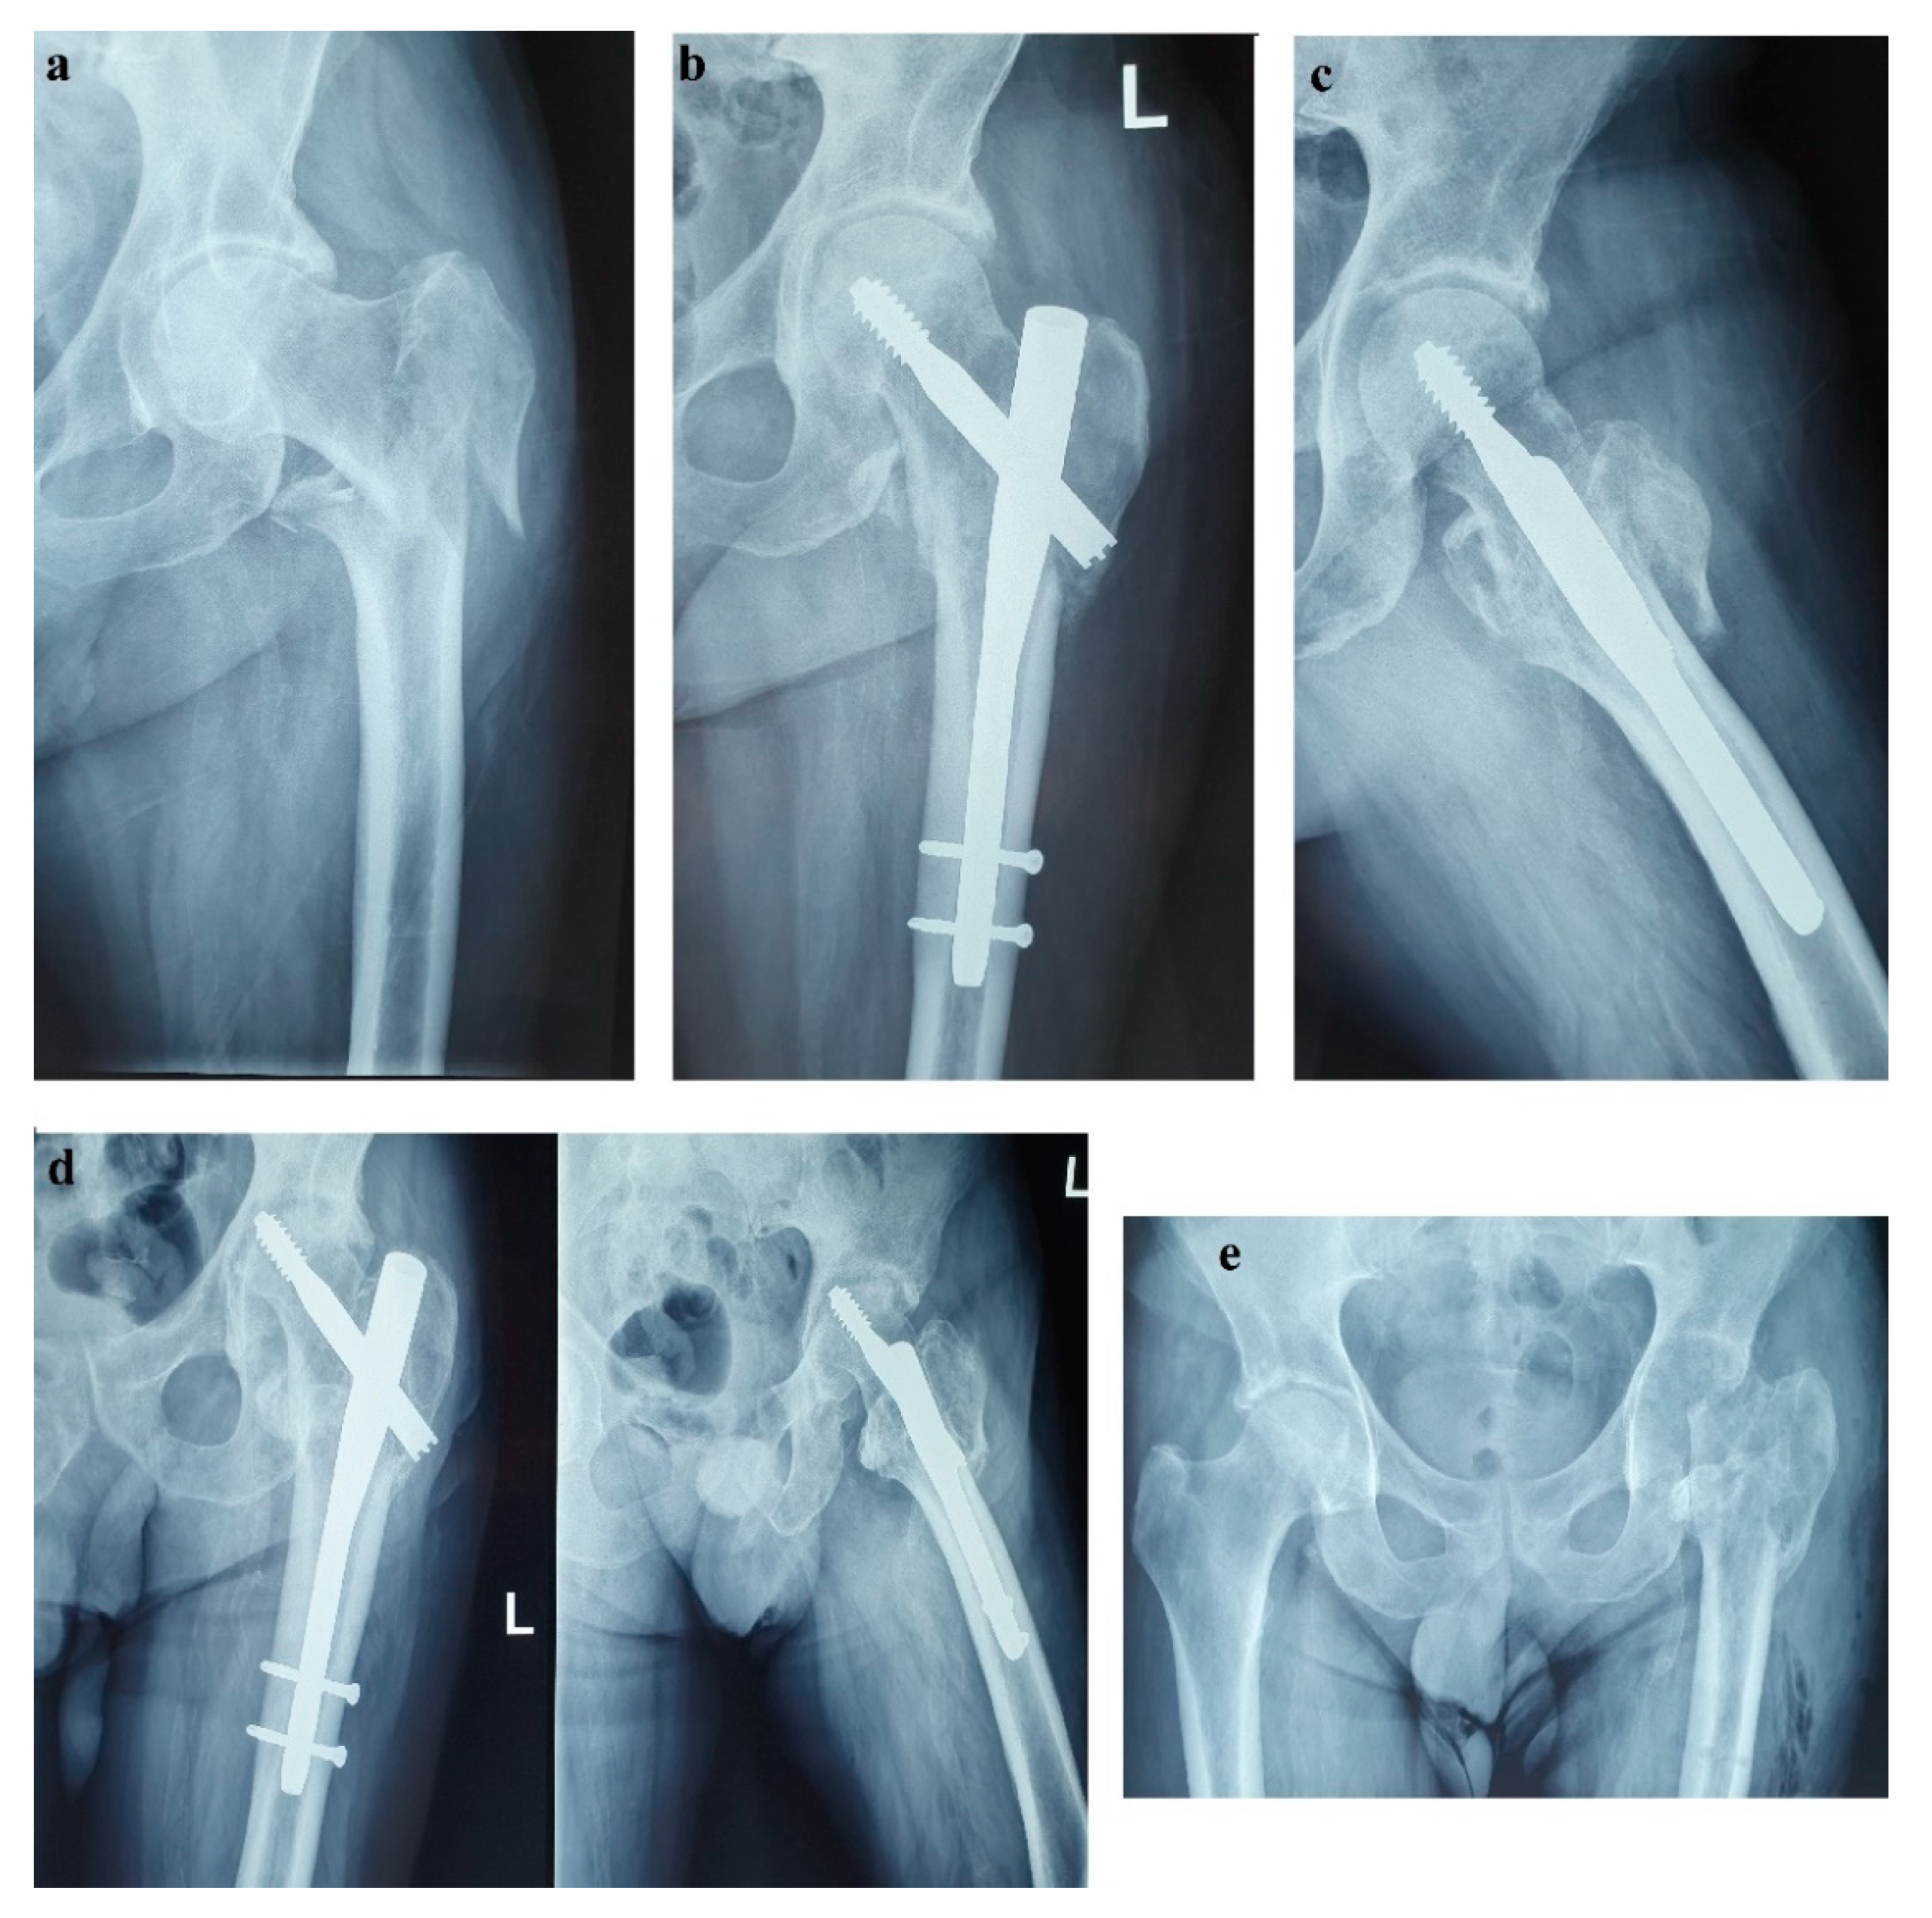

For disease staging, we performed whole body 18F fluorodeoxyglucose-positron emission tomography (FDG-PET)/CT, which revealed a 34/38 mm hypermetabolic (standardized uptake value (SUV) = 6.67) tumor in the pancreatic tail and satellite solid tumors nearby the primary tumor with no uptake of F-18 FDG. There was no imaging proof of systemic metastases. Using whole body 99mTc-EDDA/HYNIC-Tyr3-Octreotide scintigraphy (SRS) with single photon emission tomography (SPECT-CT) acquisition we noticed a 41/33 mm well-circumscribed pancreatic tumor with high radiotracer uptake. The pancreatic tumor was the only situs for the radiotracer uptake (Figure 5).

For further tumor characterization, we decided to use EUS, which also confirmed a 35/39 mm hypoechoic, heterogenous mass in the tail of the pancreas that expanded into the splenic hilum with peripheral hypervascularization. The EUS-FNA and pathological analysis revealed nests of uniform round cells with monotonous nuclei, without evident mitoses in hematoxylin and eosin staining. Immunohistochemical staining was positive for CgA, synaptophysin, and cytokeratin AE1/AE3 with a Ki67 proliferation index of 2%. As far as we knew, we were facing a TNM stage III, well-differentiated, low grade, G1, sporadic, functional pNET with regional lymph node involvement [18].

Figure 5. Head-to-head comparison of 99mTc-EDDA/HYNIC-TOC SPECT/CT SSTR scintigraphy and 18F-FDG PET/CT on the (a,b) MIP images and (c,d) fused axial images with high uptake of both radiotracers (radiolabeled somatostatin analogue and glucose analogue, respectively) in the pancreatic tail tumor (arrows) and no uptake in the satellite tumor (described on contrast-enhanced CT) or elsewhere on whole body images. 99mTc-EDDA/HYNIC-TOC SPECT/CT SSTR scintigraphy and 18F-FDG PET/CT fused coronal images: (e,f) higher uptake of radiolabeled somatostatin analogue compared to glucose analogue in the pancreatic tail tumor (arrows).